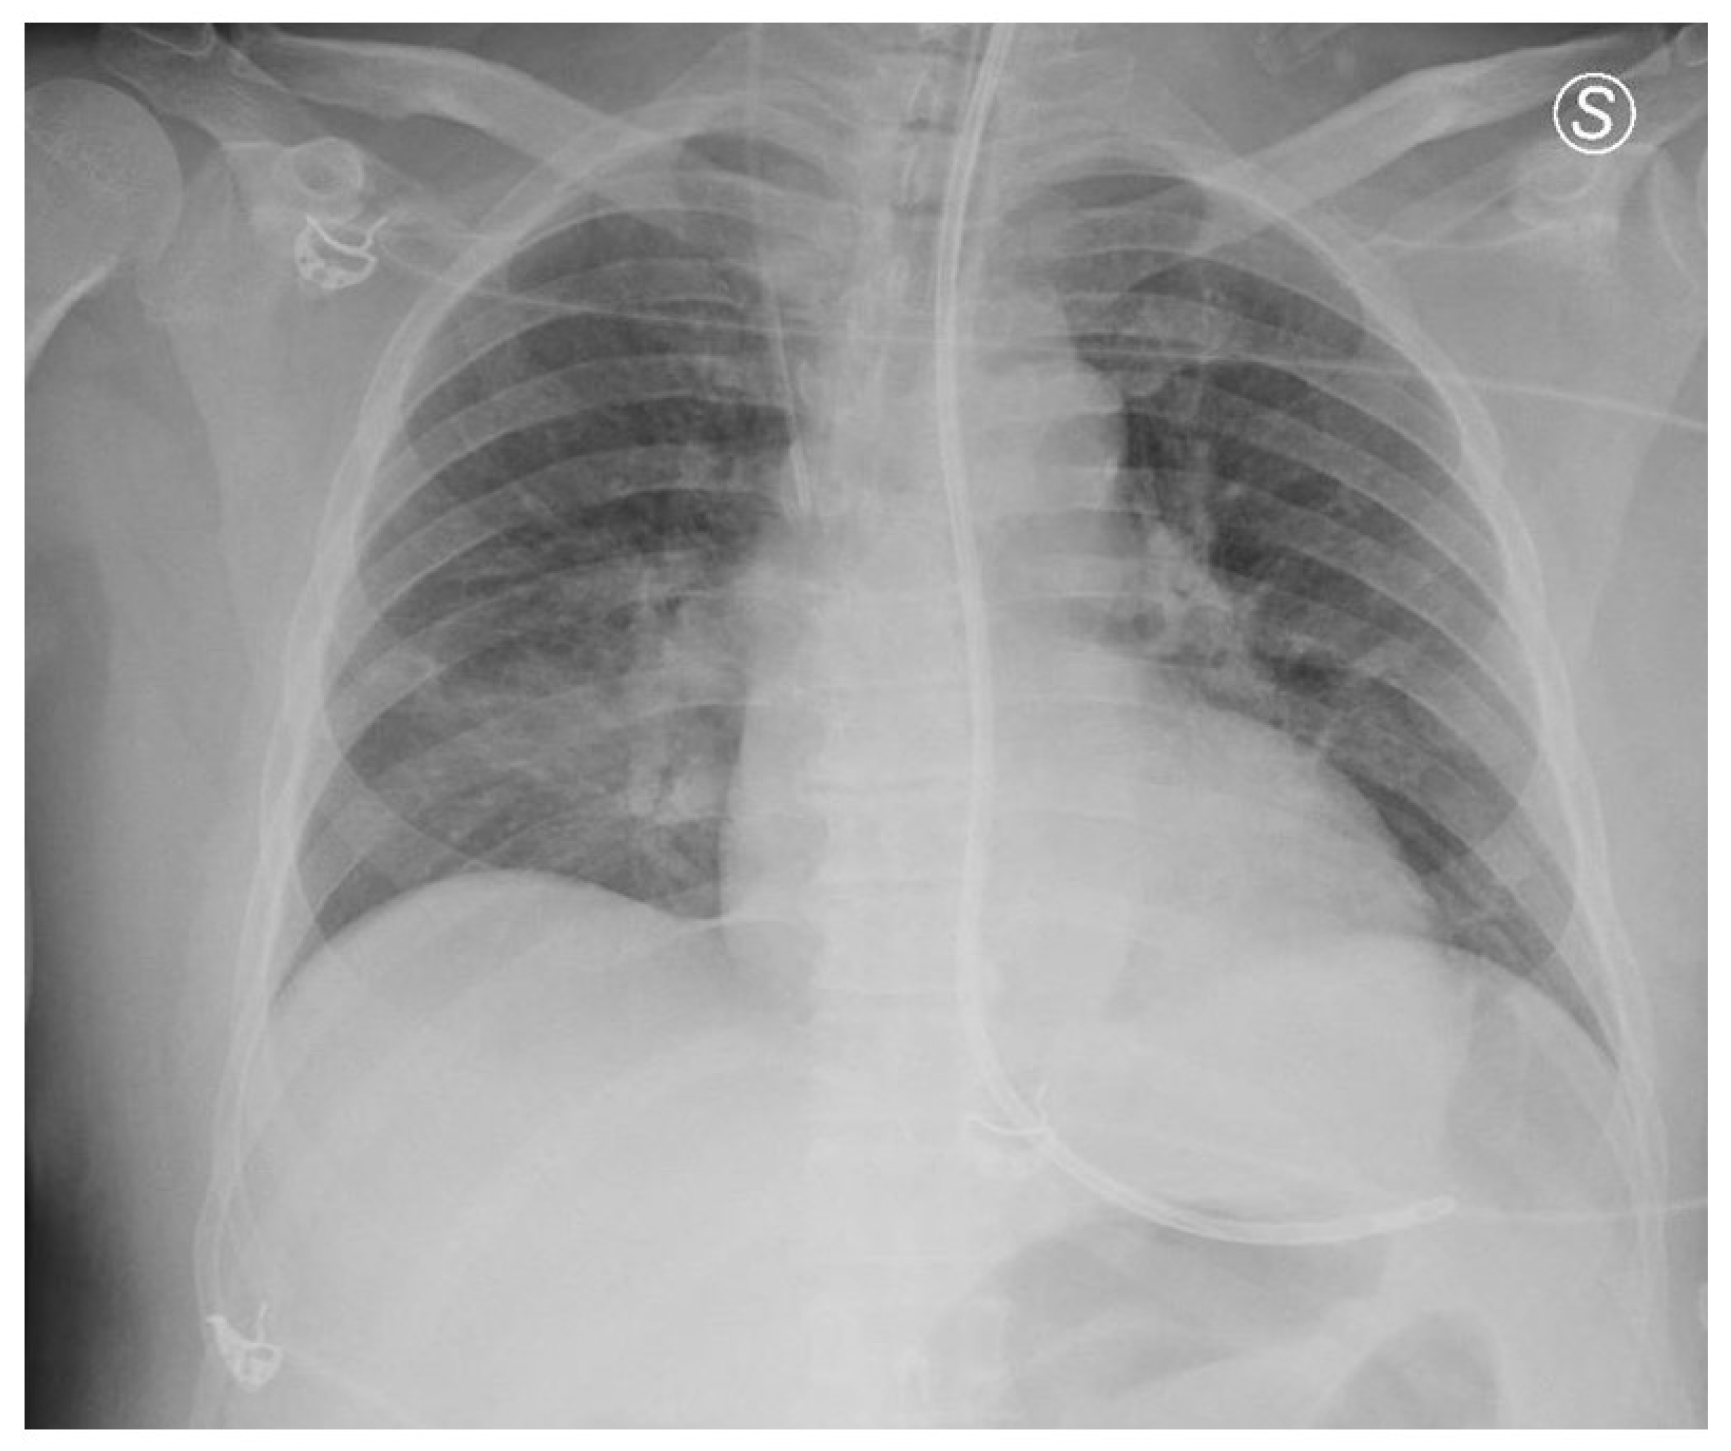

The patient remained mechanically ventilated and was fed via a nasogastric (NG) tube. On the tenth day of ICU admission, the advanced state of coma persisted [GCS 3—E(1) V(NT) M(2)], with miotic, isocoric, and isocyclic pupils that were weakly reactive to light stimulation. Neurological examination revealed the presence of bilateral corneal reflexes, a cough reflex, a preserved doll’s eye reflex, and an indifferent plantar reflex. An electroencephalogram (EEG) performed during this period showed increased slow-wave activity without irritative elements. A few days later, a new chest X-ray was performed due to elevated inflammatory markers. The imaging confirmed the presence of the NG tube, with its distal end projecting into the likely location of the gastric body. Additionally, an area of pulmonary hypodiaphany was identified in the right middle lung field (Figure 2).

Figure 2.

Chest X-ray demonstrating the presence of an NG tube, appropriately positioned in the likely region of the gastric body. Additionally, an area of pulmonary hypodiaphania is observed in the right middle lung field, suggestive of potential pathology. S: Left.